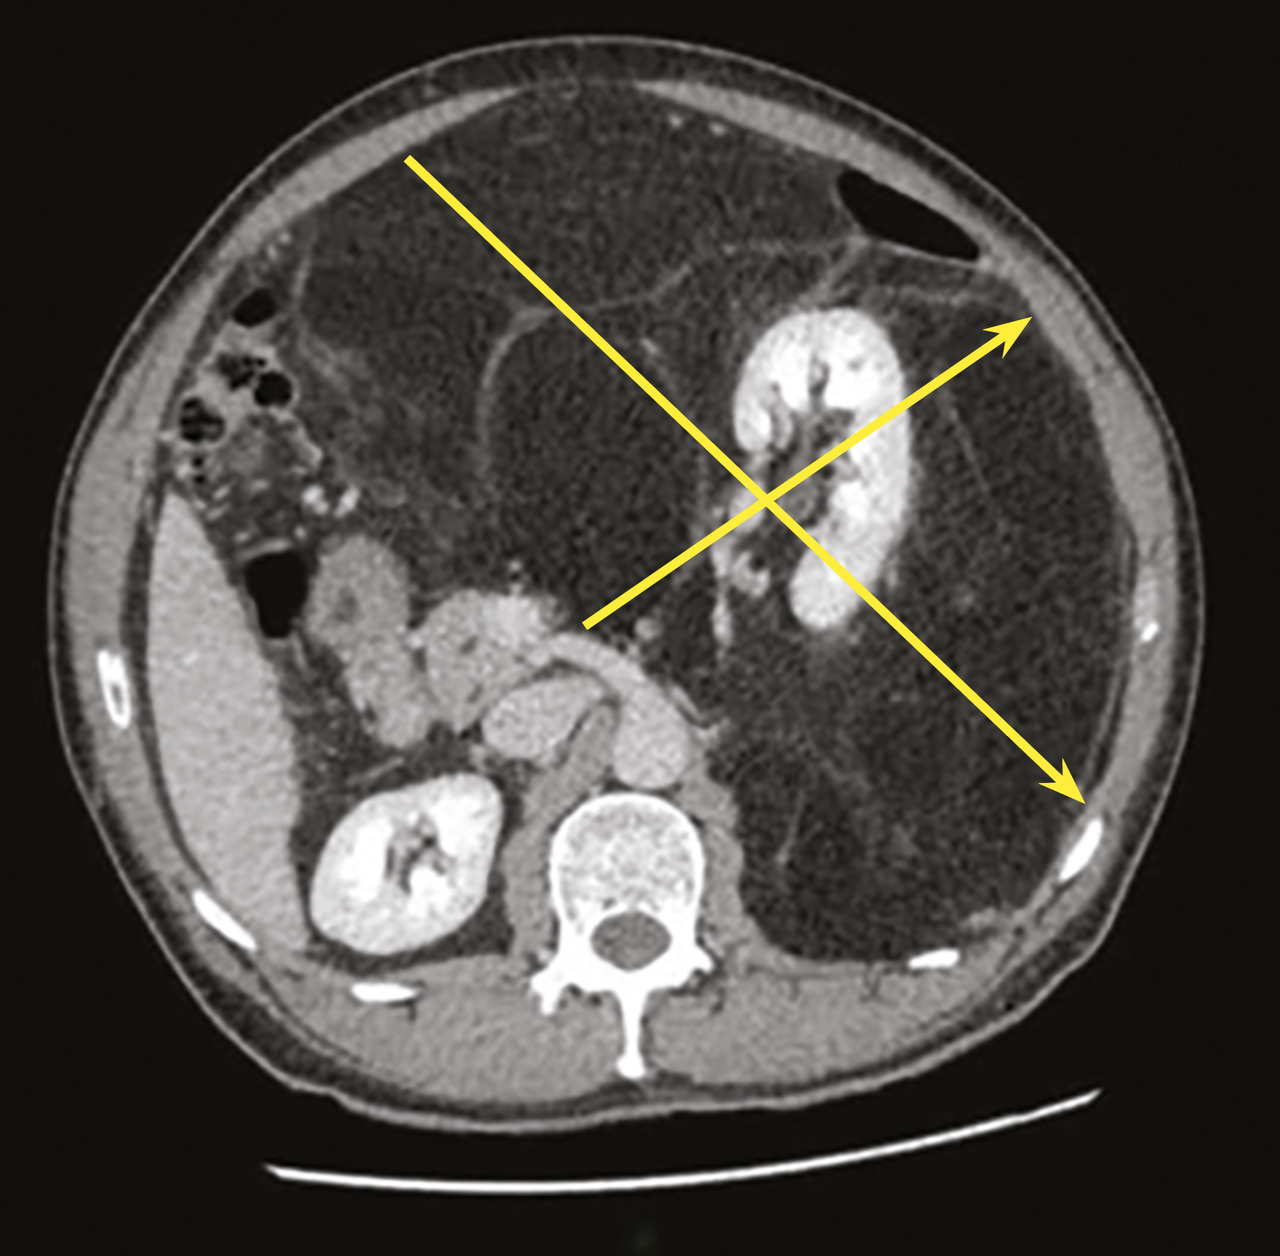

Les critères de qualité de la chirurgie des sarcomes rétropéritonéaux sont d’une part une exérèse en un bloc et d’autre part des marges saines sur la plus grande superficie (fig. 2).11 Il ne faut pas faire de biopsie chirurgicale par cœlioscopie ou laparotomie car cela correspond à une effraction tumorale.8,11 Si le patient a été opéré d’emblée sur un diagnostic erroné de tumeur intrapéritonéale (sur une hypothèse de tumeur de l’ovaire, par exemple) et que l’on constate que la tumeur est rétropéritonéale, il vaut mieux refermer et prévoir une biopsie percutanée par voie rétropéritonéale ensuite. Après une exérèse fragmentaire, le patient est exposé à un essaimage péritonéal plus ou moins rapide selon le grade, et une reprise chirurgicale ne modifie pas ce risque.

Deux grandes études ont montré qu’une chirurgie dite « compartimententale » permet de diminuer d’un facteur trois le risque de rechute locale et d’améliorer la survie globale par rapport à une excision simple de la tumeur.18,19 Cette chirurgie compartimentale consiste à réséquer la tumeur avec ce qui est inclus à l’intérieur (le rein le plus souvent), en avant (le côlon et son méso) et en arrière (les aponévroses musculaires), pour optimiser les marges.8,11,20 Les structures nobles (vaisseaux et nerfs) ne sont pas réséquées si elles ne sont pas incluses dans la tumeur ou infiltrées. La chirurgie compartimentale s’applique plus particulièrement aux liposarcomes, dont le risque évolutif est essentiellement la rechute locale et dont la répétition finit par entraîner le décès du patient. En revanche, les léiomyosarcomes sont surtout exposés à un risque métastatique élevé alors que le risque de rechute locale est faible. En conséquence, leur chirurgie est plus limitée et consiste en une exérèse simple de la tumeur et de ce qu’elle infiltre directement. De même, les tumeurs rétropéritonéales à risque de rechute locale faible comme les tumeurs fibreuses solitaires ou les tumeurs malignes des gaines nerveuses périphériques peuvent bénéficier d’une exérèse simple.21